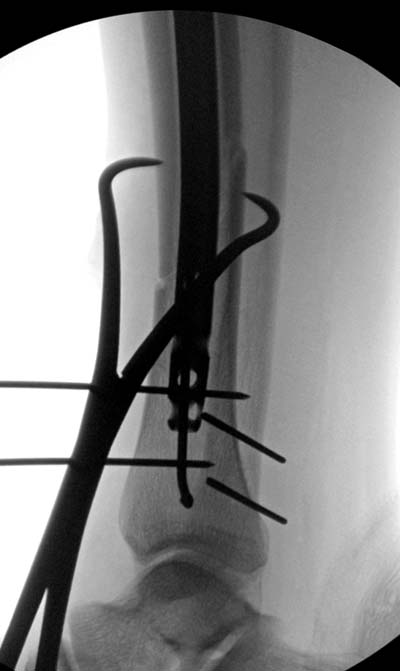

Разбор любого случая кому-то поможет лучше ориентироваться в решении вопросов, потому что в нашей работе встречаются разные связанные и несвязанные с мастерством хирурга ситуации. Возможно, отсутствие полного набора гвоздей повлияло на выбор короткого имплантата, имеется угловая и ротационная деформации. Независимо от локализации, стабильность создается, когда гвоздь проксимально не глубже 1.5 см (облегчает удаление) и дистально доходит до epiphyseal scar.

Кроме этого, имеет значение предварительная репозиция и риминг в центре канала. Интактная малоберцовая иногда затрудняет репозицию, но существуют разные приемы, нп. при застарелом можно применить дистракторы: стержневой или кольца Илизарова, а при свежих - перкутанно Weber clamp.

Мнение о том, что гвоздь сделает репозицию не всегда соответствует истине. Снимки показывают на неудачную попытку исправить направление гвоздя с помощью “поллеров”. Прием возможен только тогда, когда проход риминга в центре канала, иначе толкать гвоздь некуда.

Здесь несколько снимков изолированного перелома большеберцовой с интактной малоберцовой. Weber clamp, блокирующие спицы и риминг в центре канала отрепонировал перелом....